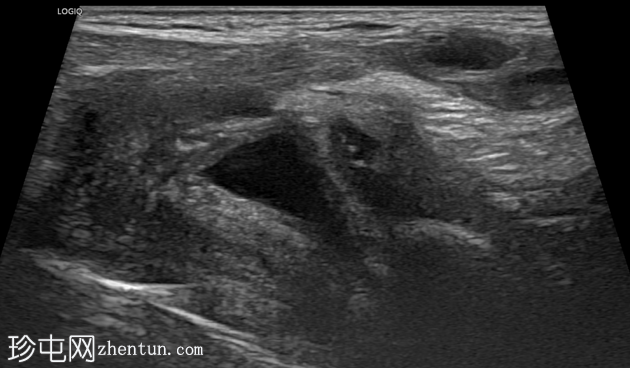

横切面

纵切面

右侧努克氏疝管长约6毫米,内含部分子宫和卵巢(大小约1.5 x 1厘米)。在整个检查过程中,这些组织均保持原位。

对侧附件呈多囊性改变,大小约3 x 1.8厘米。

膀胱外观大致正常。

上述超声特征清晰地显示了努克氏疝管的内容物及其延伸范围;其中包含患者的一侧卵巢和部分子宫组织。

这些特征符合卵巢努克氏疝的诊断。